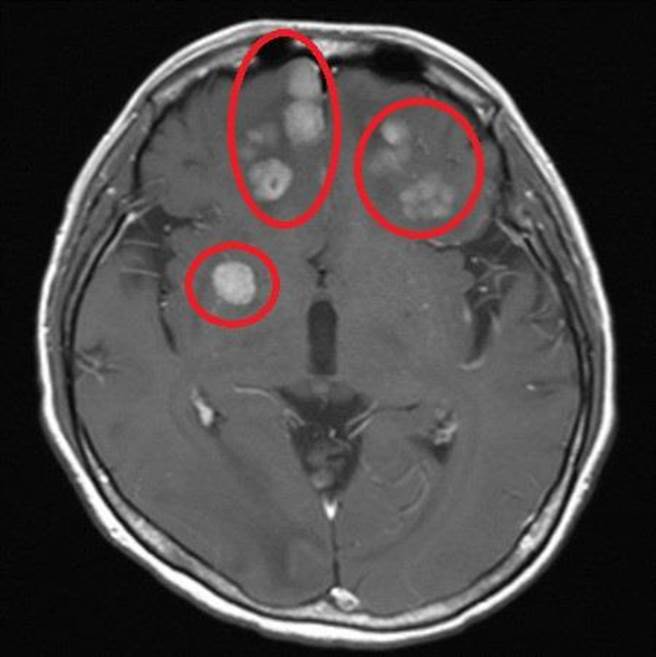

电脑断层显示,患者尚未接受抗体复合药物治疗前,脑部扩散的癌细胞。(台北慈济医院提供)

40岁的刘小姐因触摸到胸部不明肿块而至他院就医,并接受手术及荷尔蒙治疗,却在2021年復发,于是来到台北慈济医院就诊,被诊断出属于三阳性乳癌,且癌细胞已扩散至肺、肝、骨骼以及脑部,导致患者经常抽筋而造成行动不便,严重时还发生病理性骨折的状况。

张耀仁副院长决定予以新型的抗体复合药物,加上放射性治疗,半年后,脑部转移肿瘤明显缩小,刘小姐已能自由行走,癌指数也回到正常范围内。